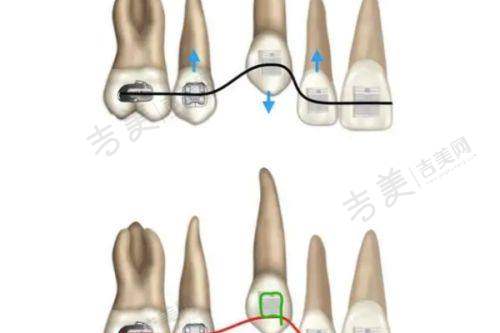

烟台德韩万达院口腔门诊部成立于2018年,公司人员规模少于50人,参保人数40人。门诊部规模适中,却有着完善的科室设置。开设了口腔种植、口腔正畸、口腔修塑、口腔美白、牙周中 心、儿童齿科等多个科室。以“口腔养护生态圈”为理念,致力于“养护胜于调节”的科学口腔保健观念的普及。在口腔种植方面,有着成熟的技术和丰富的经验,能够为患者提供多种种植方案;口腔正畸科室可以针对不同年龄段和牙齿畸形情况,制定个性化的矫正方案;儿童齿科则专门为儿童提供专精的口腔诊疗和预防保健服务,让孩子们从小养成良好的口腔卫生习惯。

烟台德韩万达院口腔门诊部拥有众多特色项目。即刻种植牙是其一大亮点,该技术能够在拔牙后立即植入种植体,大大缩短了治疗周期,减少了患者的痛苦。美国3种种植体和瑞士ITI种植体,为患者提供了更多的选择,这些种植体具有良好的生物相容性和稳定性,能够确保种植成效。氟斑牙治疗采用精良的技术和方法,有效改善牙齿外观和色泽。儿童龋齿治疗针对儿童牙齿特点,采用温和、微痛的治疗方式,让孩子轻松摆脱龋齿困扰。地包天矫正项目,医生会根据患者的具体情况制定个性化的矫正方案,帮助患者修复正常的咬合关系。洗牙项目采用精良的设备和技术,能够有效清除牙齿表面的污垢和菌斑,预防口腔疾病。口腔预防保健则注重从源头预防口腔问题,为患者提供专精的口腔卫生指导和建议。拔牙、牙套、活动义齿、牙齿美白等项目也都有着专精的医生团队和精良的技术设备支持,能够为患者提供优质的诊疗服务,充分体现了烟台德韩万达院口腔门诊部的实力。